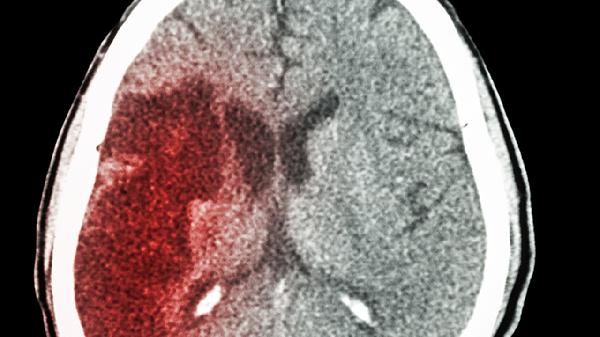

它会干扰凝血机制,使血小板更容易聚集。临床数据显示,HCY每升高5μmol/L,脑梗风险增加59%。